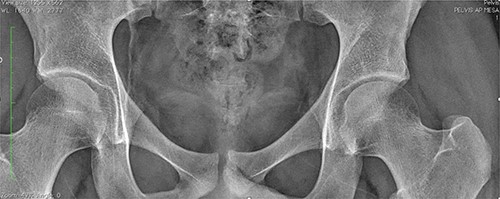

An 18-year-old male with 18 months of left hip pain was referred to an orthopedic surgeon for evaluation. Pain occurred with all hip movements, predominantly at night. Physical examination of the hip showed pain with deep palpation on the groin and positive test for flexion adduction and internal rotation and Patrick test. X-rays were obtained and femoroacetabular impingement (FAI) with labral tear was suspected (Fig. 1). A magnetic resonance imaging (MRI) showed no hip labrum or chondral defect. Measurements for bone deformities of cam and pincer were normal. Physical therapy and nonsteroidal anti-inflammatory drugs were prescribed with some pain relief especially at night. After no improvement of symptoms he was evaluated by a hip surgeon. Intra-articular hip injection with steroids was given and pain disappeared but nocturnal pain recurred after 24 h. Due to the clinical setting and poor response to pain management, an OO was suspected and (CT) was ordered where a 6 mm sclerotic bone tumor with a nidus in the anterior rim of the left acetabulum was identified and corresponded with the pain localization (Fig. 2).